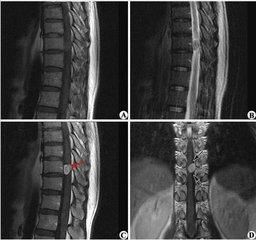

臨床表現隨其大小與部位而異,小腫瘤可無症狀,較大者因受累神經受壓而引起麻痹或疼痛,並沿神經放射。顱內聽神經瘤可引起聽覺障礙或耳鳴等症狀。大多數腫瘤能手術根治,極少數與腦幹或脊髓等緊密粘連未能完全切除者可復發,復發腫瘤仍屬良性。